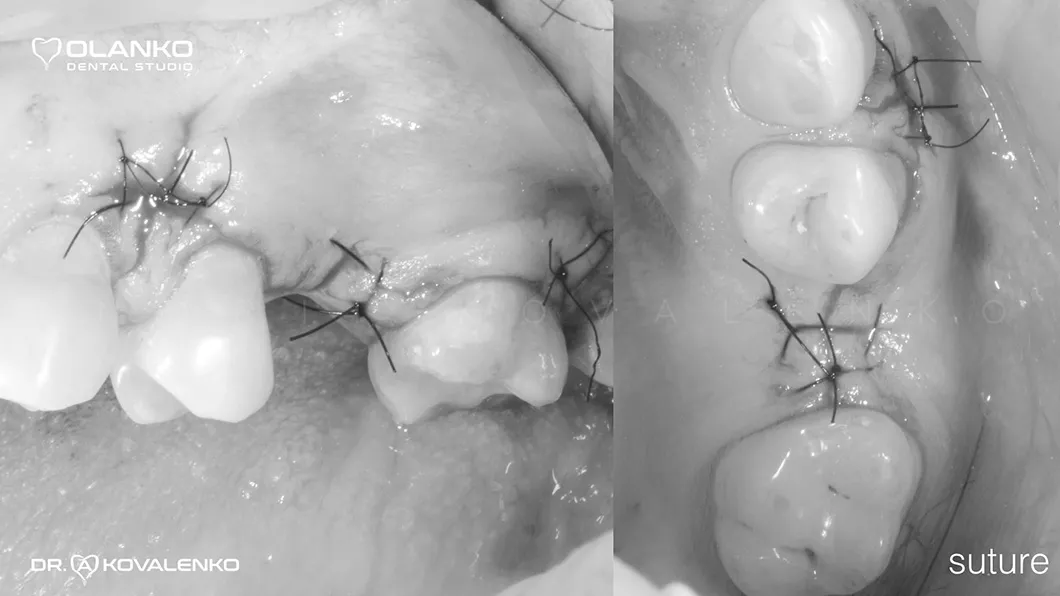

Операція кісткової пластики може виконуватися як самостійно, так і спільно з встановленням зубного імплантату.

Кісткова пластика методом відкритого синус-ліфтингу

*Фотографії з наявністю крові були переведені в чорно-білий формат